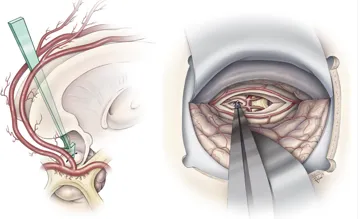

在颅咽管瘤术前考虑中,需要着重考量肿瘤的主要位置(交叉前、鞍后、交叉后),以及肿瘤与交叉、下丘脑附着的关系,垂体漏斗和垂体柄的位置,大而复杂的肿瘤可能需要联合不同入路手术。

颅咽管瘤手术首要目标是安全、彻底地到达并切除肿瘤;其次,要尽可能保留垂体柄。之所以要重点保护这两者,是因为它们对于患儿未来的生活质量极为重要。垂体柄涉及激素的分泌,下丘脑则像汽车的刹车和油门,负责调控激素分泌的节奏。

除此之外,手术还必须在不损伤视神经等关键结构的前提下,尽量实现肿瘤的全切除,防止复发。对于颅咽管瘤手术来说,保护垂体柄和视神经功能的完整是主要的,如果能在这一前提下实现完全切除,则达到了理想的效果。